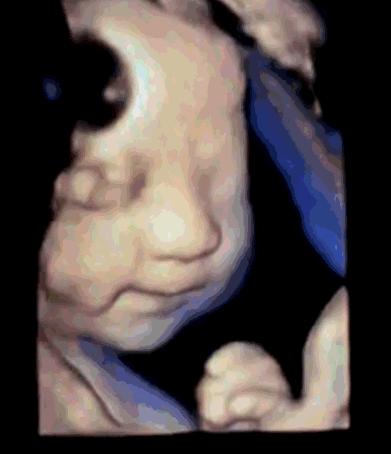

孕妇春儿自从怀孕后,她就一直在家休养。因为第一次当妈妈,所以她对于胎动十分的好奇。

怀孕16周,她感受到胎儿的第一次胎动,真的是欣喜若狂,胎动让她感受到了做妈妈的喜悦。怀孕20周,胎动还没有形成规律,她总是要感觉到胎动,心里才踏实,每天她都会很认真地数胎动,还会把每小时的胎动数记录下来。

如今怀孕7个月,她发现一个很奇怪的现象,胎动不但十分的活跃,而且总是出现在孕肚的右侧,让她十分的疑惑,胎儿为什么偏爱右侧,老是右边胎动?7个原因要搞清,最后一个很暖心。